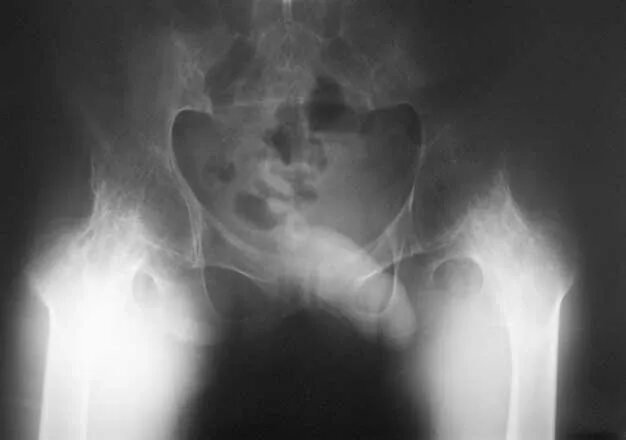

Анкилоз тазобедренного сустава